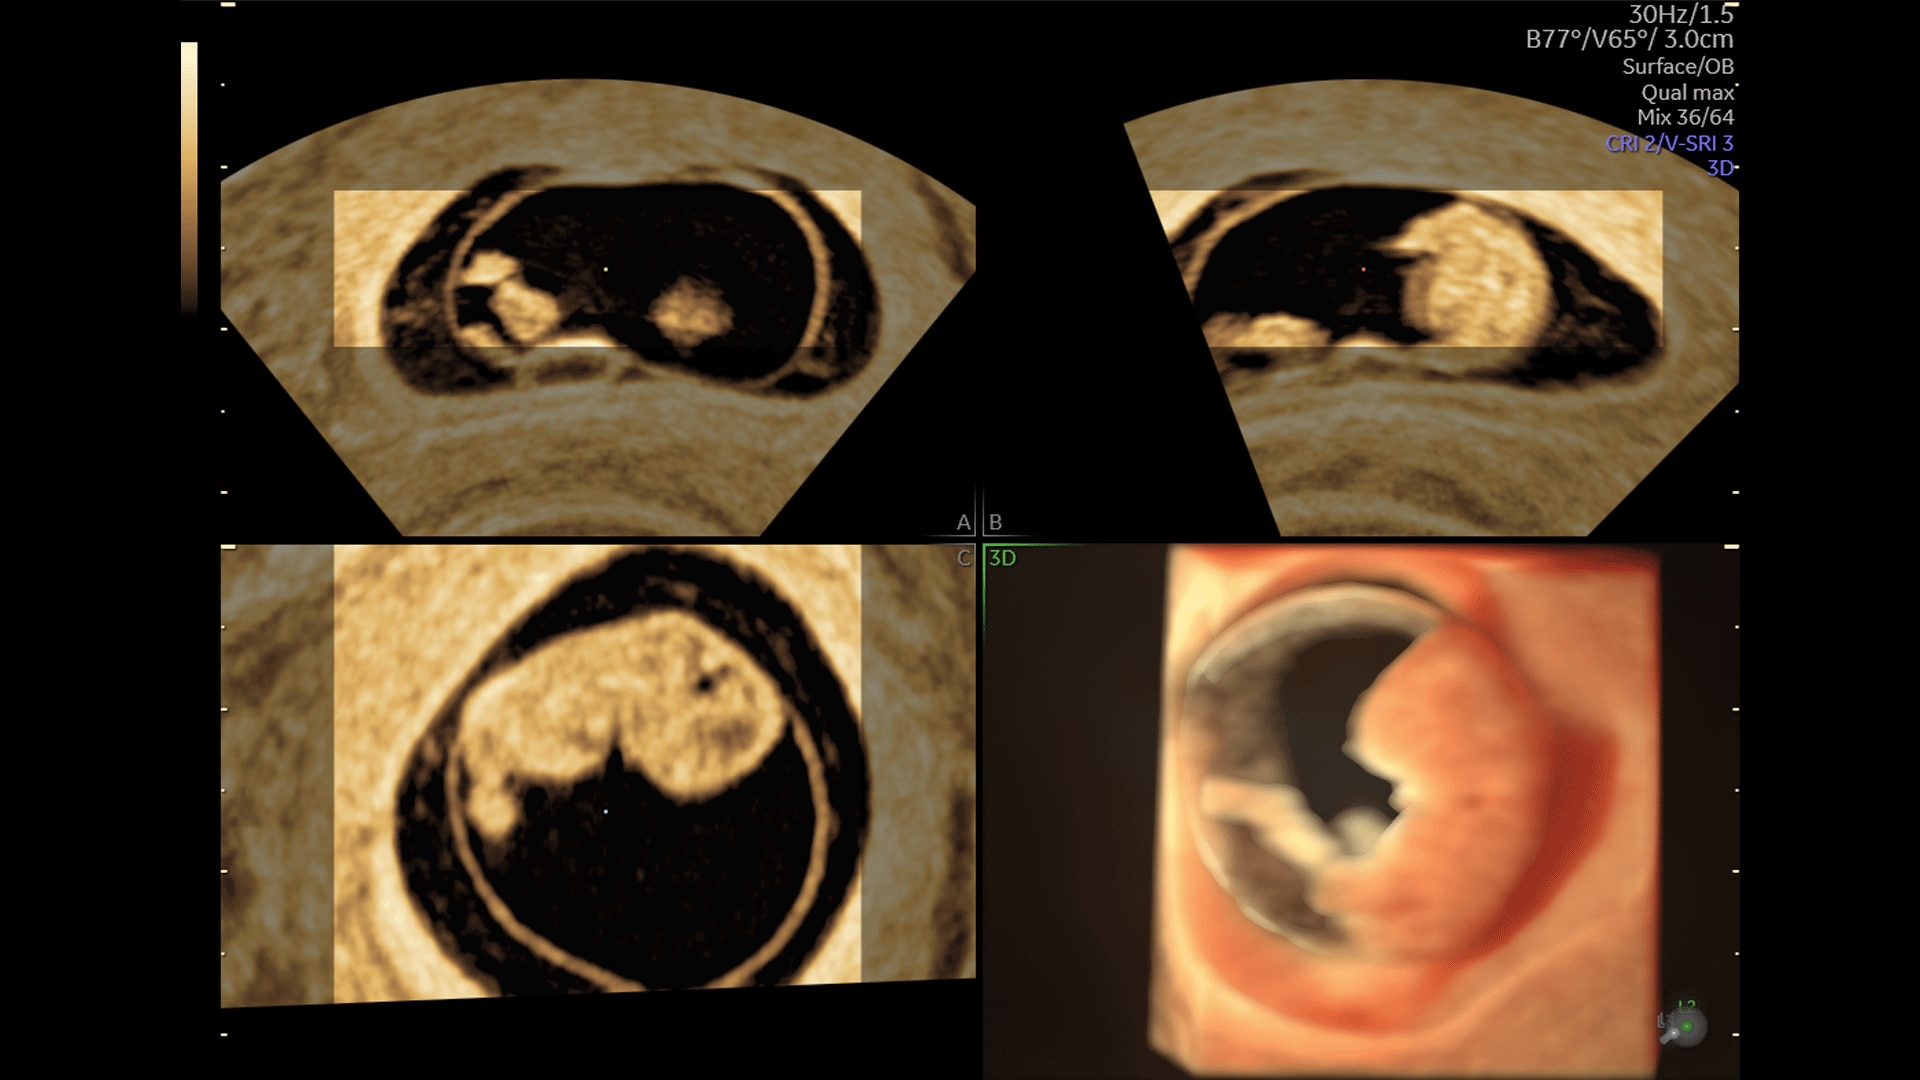

Amplify imaging performance and simplify scanning with our most advanced architecture

Extraordinary clarity and definition so you can focus on early detection and intervention.